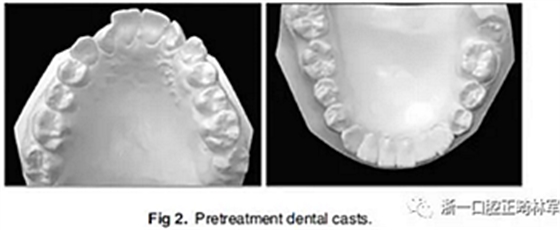

口內(nèi)分析顯示呈II類1分類錯合畸形,前牙開合2mm和覆蓋3mm(圖2)。左側(cè)的后牙存在反合。上牙弓擁擠度2.5mm,下牙弓擁擠度1mm。中線一致。下頜前牙區(qū)牙齦稍有退縮。